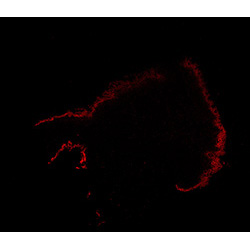

An anatomical analysis of the developing human midbrain from 6 post-conceptional weeks (PCW) to 22 PCW reveals increased tissue complexity, characterized by the emergence of dopaminergic nuclei, as highlighted by immunofluorescence analysis for tyrosine hydroxylase (TH).

TH

6PCW human midbrain